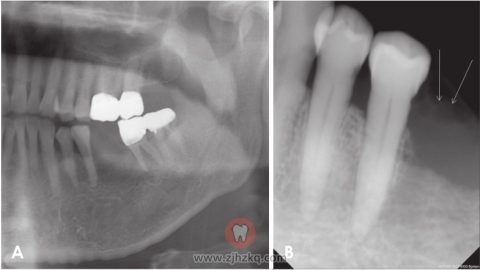

图6.全景片显示,种植体周围有边界不清的骨质破坏。根尖片显示增大的软组织影。

图7.A.B超显示边界清楚的不均匀肿块(30 mm×15 mm),可见局限性骨质破坏。B.彩色多普勒超声图显示新形成的血管供应肿块的内部及周边。